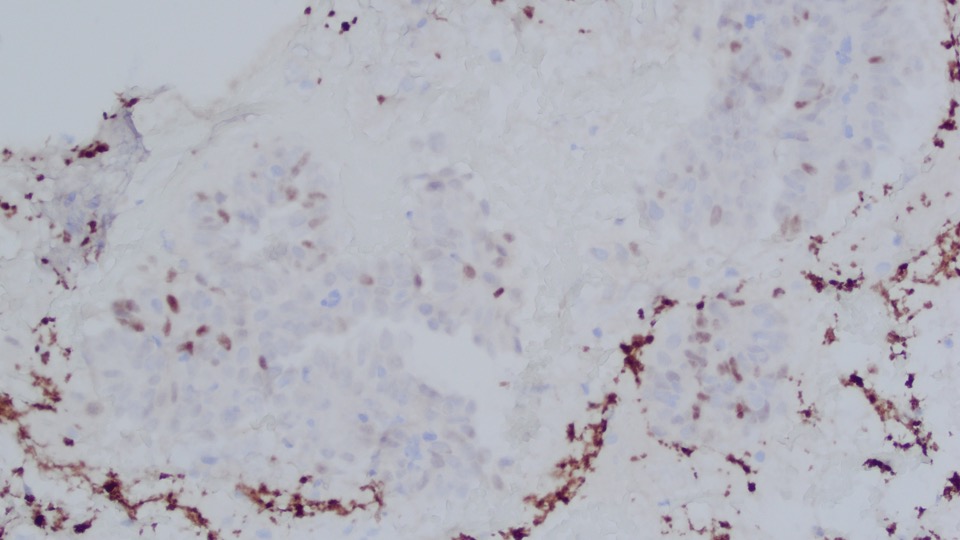

The papillary proliferation is positive for PAX8 (strong), ER (strong scattered), and p16 overexpression; and negative for Napsin A and AMACR. p53 shows wild-type expression pattern.